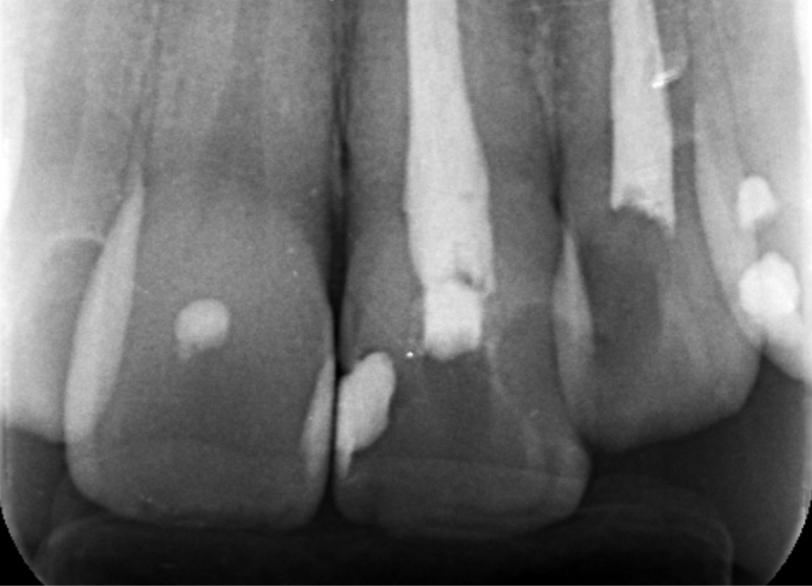

| 診断 | 失活による歯の黒色変化 | ||

| 処置内容 (または主訴) | 失活歯に対するウオーキングブリーチ | ||